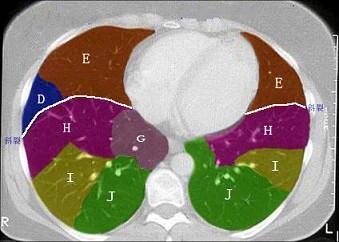

结合肺段模式肺动脉干与右肺动脉层面(如图),选出右肺中叶的组成 ( )A.BB.B+CC.B+C+DD.D+EE.D+E+F

问题 结合肺段模式肺动脉干与右肺动脉层面(如图),选出右肺中叶的组成 ( )

选项 A.B B.B+C C.B+C+D D.D+E E.D+E+F

答案 D